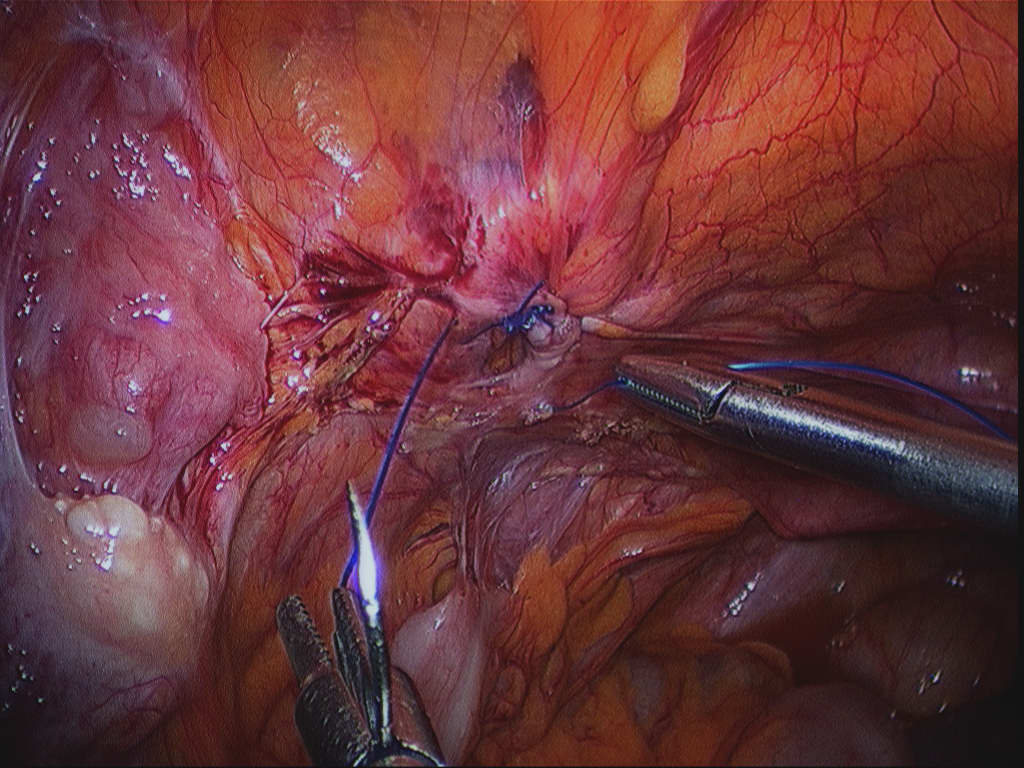

Endoscopio laparoscópico (Nuevo) $ 15,999.00 MXN en Masaya, Nicaragua - Venta Local Buscas